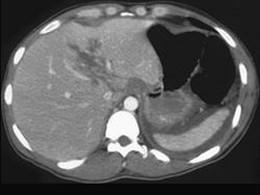

男,42岁,肝区钝器伤后2小时,CT扫描如图,最可能的诊断是 ( )A、脂肪肝B、肝内胆管扩张C、肝淋巴管瘤D、肝挫裂伤E、肝胆管细胞癌

问题 男,42岁,肝区钝器伤后2小时,CT扫描如图,最可能的诊断是 ( )

选项 A、脂肪肝 B、肝内胆管扩张 C、肝淋巴管瘤 D、肝挫裂伤 E、肝胆管细胞癌

答案 D